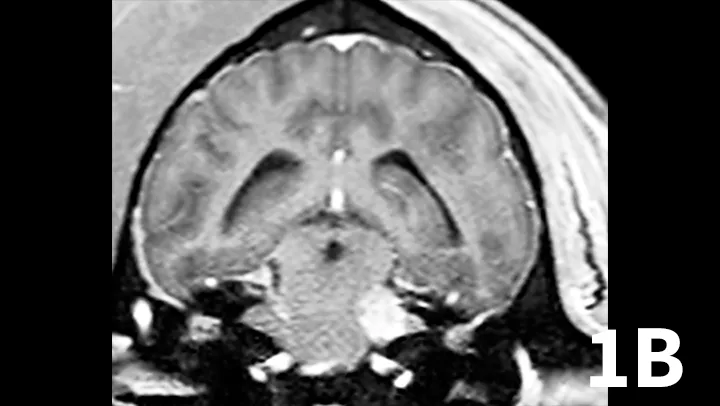

Animals may have erythema and pruritus affecting the external ear or pinna, odor or discharge from the ear, and pain in addition to signs of peripheral vestibular disease. Although diagnosis can be suggested by otoscopy, advanced imaging is superior, as it permits visualization of the osseous bulla and inner ear. The author typically prefers MRI to image dogs suspected of otitis interna because it is superior to computed tomography (CT) for detecting intracranial extension of lesions and detecting other causes masquerading as otitis interna. On MRI, bullae may appear thickened and are usually filled with T2-hyperintense/T1–iso-hypointense (dark) material; abnormal tissue within the bulla usually contrast-enhances T1WI (Figure 2). On T2WI, there may be a loss of signal within the inner ear. Myringotomy and deep ear flush are recommended to identify the underlying infectious agent and assist in removing debris or pus that will prohibit clearance of infection. Antimicrobial therapy is typically continued for 6 to 8 weeks, as bone infection is likely.

Transverse T2WI (A) and T1WI (B) from a 6-year-old cocker spaniel with a 6-month history of left peripheral vestibular disease that acutely worsened, with signs consistent with central localization. The left middle ear cavity is filled with T2-hyperintense material (arrowhead). The left inner ear is hypointense (arrow) compared with the right side. In addition, the left medulla and cerebellum contains patchy T2-hyperintense lesions. T1 postcontrast images show enhancement of the meninges (arrowhead) and a mass-like, enhancing lesion adjacent to the internal acoustic meatus. These findings are consistent with chronic otitis interna and media with secondary extension into the meninges and central nervous system.